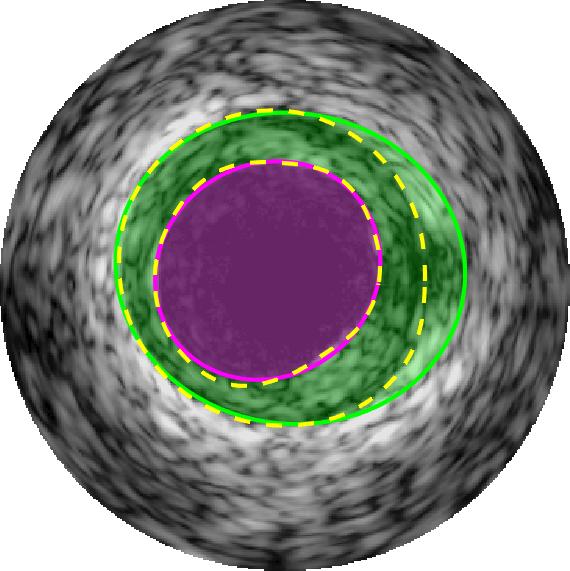

Qualitative evaluations are illustrated in Figure 4 and show the successful segmentation results of the proposed EREL selection strategy for 20 IVUS frames. The lumen areas are highlighted by the magenta colour while the media regions are green. Also, the manually annotated contours for both lumen and media are drawn as yellow dashed lines. As we can see, the chosen frames contain a variety of lumen and media morphologies.